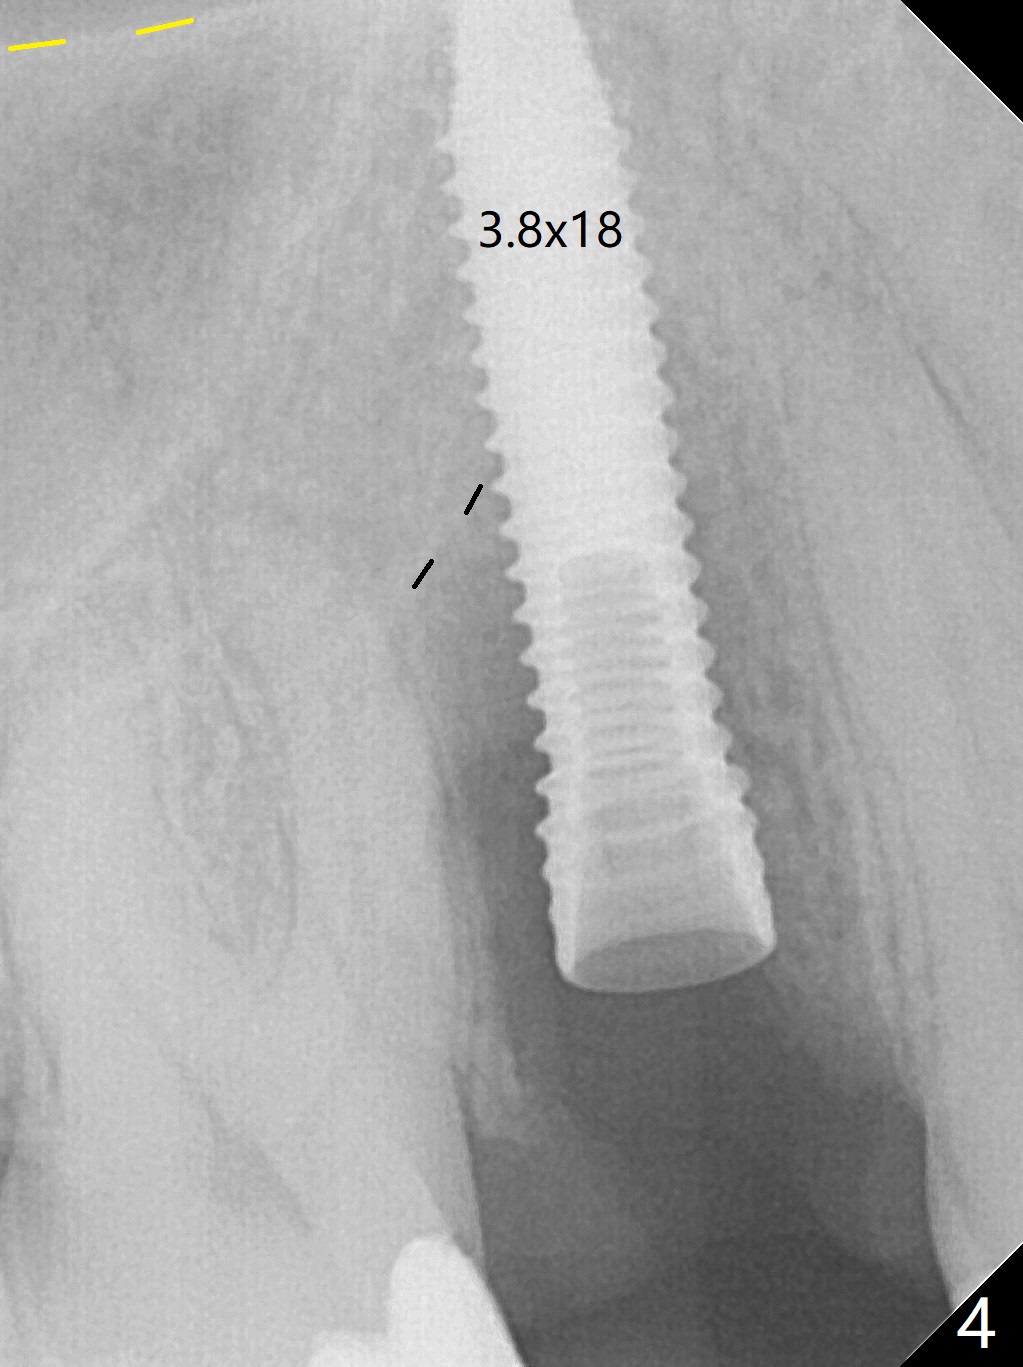

When the tooth #4 with vertical root fracture (Fig.1) is extracted, the buccal plate is found to be lost. The lowest point of the defect is shown as black dashed line in Fig.2 (yellow dashed line: sinus floor). After use of 2.5 mm reamer for 21 mm (buccal gingival level) and 3.0 mm reamer for ~17 mm, a 3.8x15 mm dummy implant is placed with 30 Ncm and 1.85 mm apical space (Fig.3 pink outline). A 3.8x18 mm (definitive) implant is placed with <40 Ncm with the implant plateau apical to the lingual crest (Fig.4,5). The buccal plate defect is repaired by Vanilla Graft (Fig.6 *) before and after insertion of a 4.5x4(3) mm abutment. The buccal plate defect seems to being repaired 4 months postop (Fig.7). Occlusal wear suggests bruxism, which is also associated with the root fracture. Night guard is recommended. The defect repair is close to completion 8 months post cementation (Fig.8). The crown/abutment is found to be loose 1 year 4 months post cementation and retightened without checking whether there is clinical 2nd DO caries of #3 (Fig.9, "sensitive to water pik"). A few days later, DO composite is being removed. It is difficult to determine whether the 2nd DO caries or gap has been removed with the neighboring crown in place. When the crown/abutment is removed and gingival retractions are inserted, there is no decay. The gap is removed. With Toflemire in place, the crown/abutment is reseated and hand tightened; after packable composite, the crown/abutment is removed, there is no more DO gap.